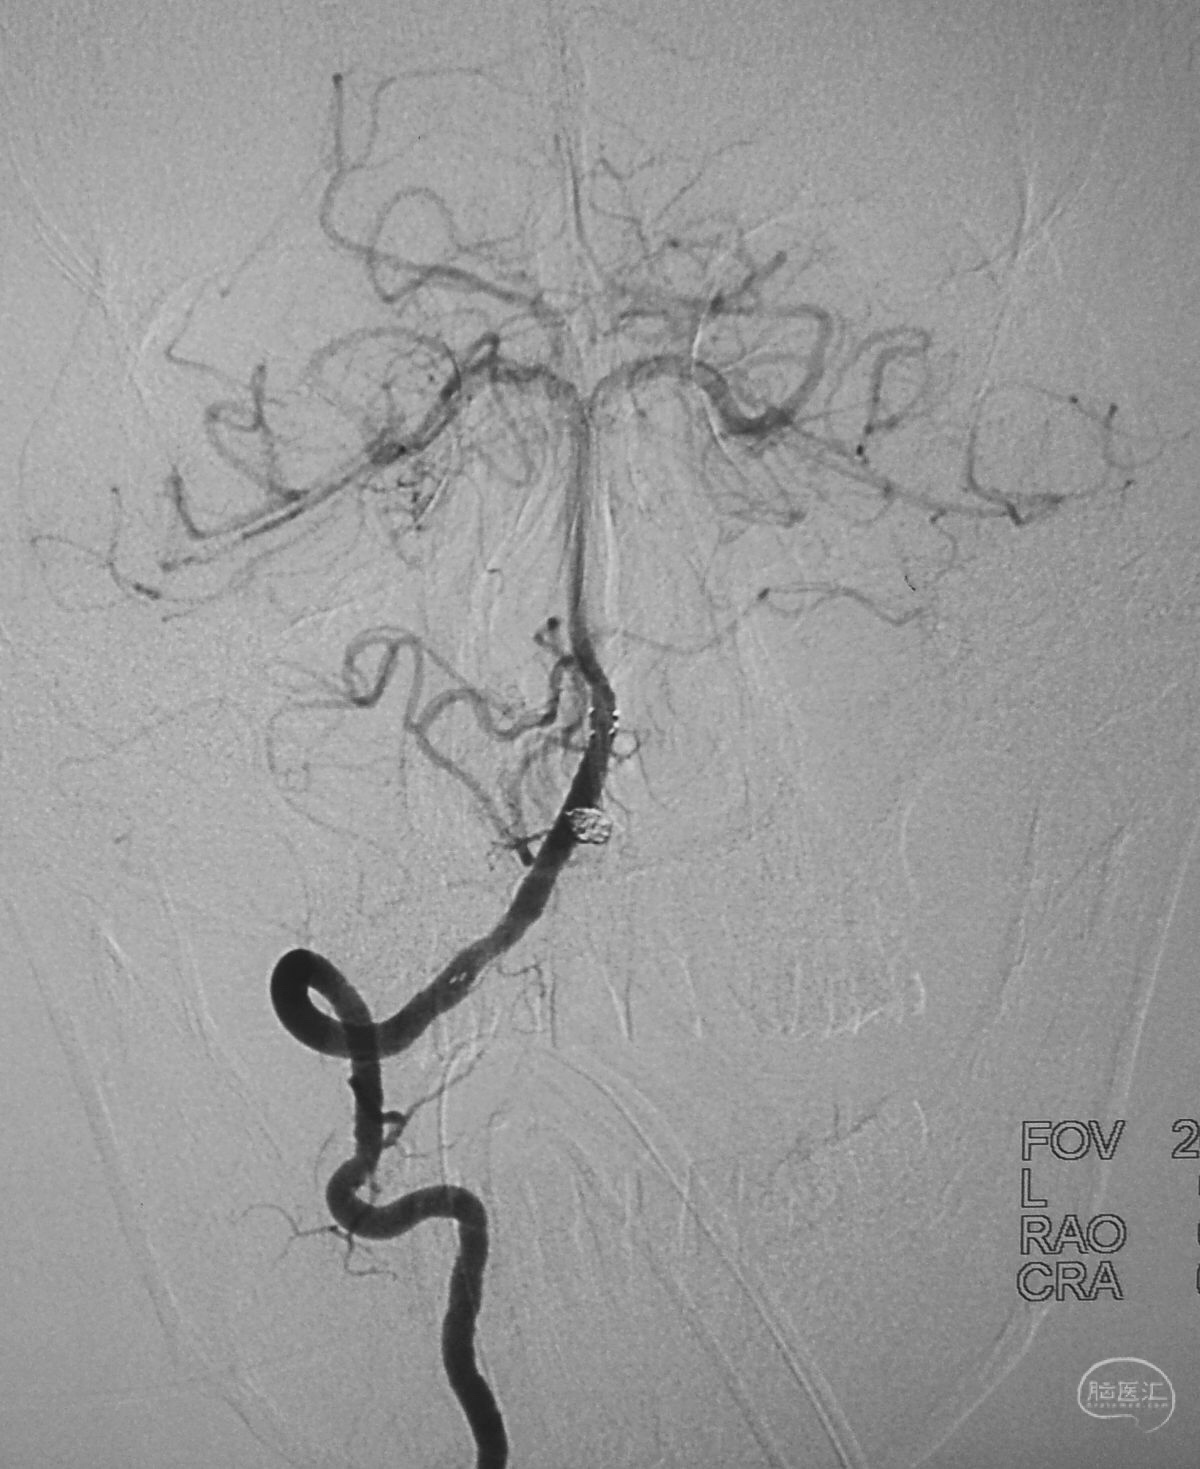

病例一,左侧微小眼动脉瘤,未破裂。

测量:瘤体2.09×2.34 mm,颈宽2.66 mm。

工作位造影

Traxcess 14微导丝可以进入瘤腔,但头端塑成S形的Echelon 10微导管无法跟入。

将微导管在虹吸弯处成襻,越过瘤颈,管头折返钩入瘤腔,即所谓回马枪技术。

Solitaire 4×15支架(绿线)跨瘤颈半释放,压住微导管(红线)。

经微导管向瘤腔内送入首枚弹簧圈(QC-2-4-3D)。

继续送入两枚QC-1.5-2-Helix,完全栓塞动脉瘤,部分圈突入载瘤动脉。

结束栓塞后不要直接撤管,要先把微导管往远心端送,使管头脱离瘤腔,再缓慢回撤。

微导管撤出后,完全释放Solitaire支架,可见突入载瘤动脉的弹簧圈被压回瘤腔。

术后左颈内动脉工作位造影和蒙片。

术后左颈内动脉造影三维重建显示动脉瘤消失。